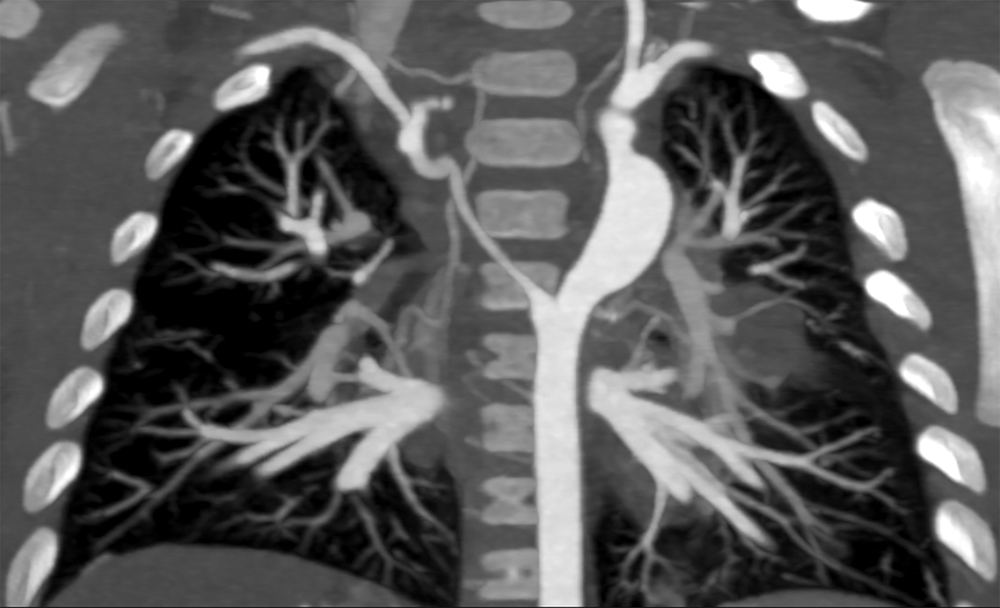

Cardiac CT (Figs. 2–4) identified an ascending aorta that gave rise to dilated common carotid arteries and an extremely tortuous and stenotic right aortic arch. The right subclavian artery originated beyond the area of severe arch stenosis with an additional area of narrowing at its origin. Collateral vessels were seen in the right side of the neck. A long and relatively narrow right-sided dorsal aortic root passed in a caudal direction where it was joined by an equally long but larger left-sided dorsal aortic root reflecting ductal flow in utero. The dorsal roots fused below the level of the carina. The descending aorta was also right-sided but crossed to the left at the level of the diaphragm. The left-sided dorsal root remnant supplied an aberrant left subclavian artery, a dilated left vertebral artery, and collateral vessels in the left side of the neck. There was no evidence of a double aortic arch.

Figure 4: An oblique coronal 3D reconstruction viewed from anterior. The ascending aorta gives rise to the two dilated common carotid arteries. A large ductal remnant is present (arrow). The left subclavian is being supplied by the left-sided dorsal root remnant